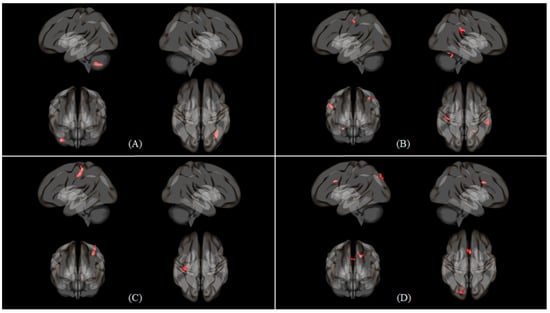

| Condition | L/R/M | Region | Cluster (KE) | Peak | Peak | Peak MNI Coordinate | ||

|---|---|---|---|---|---|---|---|---|

| T | Z score | X | Y | Z | ||||

| Nasal | R | Inferior parietal gyrus | 801 | 15.18 | 7.15 | 36 | −44 | 44 |

| Caudate nucleus | 133 | 11.33 | 7.15 | 16 | 2 | 18 | ||

| Insula | 291 | 11.26 | 6.34 | 30 | 22 | 0 | ||

| Cerebellum | 229 | 10.44 | 6.13 | 28 | −58 | −28 | ||

| Precentral gyrus | 184 | 10.17 | 6.05 | 38 | 0 | 34 | ||

| Middle frontal gyrus | 265 | 8.66 | 5.59 | 32 | 6 | 58 | ||

| M | Vermis | 413 | 9.89 | 5.97 | 0 | −66 | −34 | |

| L | Insula | 338 | 14.49 | 7.03 | −30 | 20 | 4 | |

| Precentral gyrus | 888 | 12.68 | 6.67 | −50 | 8 | 32 | ||

| Inferior parietal gyrus | 1295 | 12.68 | 6.67 | −30 | −48 | 44 | ||

| Inferior occipital gyrus | 177 | 11.42 | 6.38 | −40 | −62 | −8 | ||

| Supplementary motor area | 865 | 11.33 | 6.36 | 0 | 10 | 54 | ||

| Cerebellum | 127 | 10.39 | 6.11 | −30 | −54 | −30 | ||

| Middle frontal gyrus | 59 | 8.53 | 5.55 | −44 | 30 | 32 | ||

| Putamen | 153 | 8.24 | 5.45 | −20 | 4 | 12 | ||

| Oral | R | Inferior parietal gyrus | 568 | 11.48 | 6.39 | 36 | −46 | 46 |

| Putamen | 191 | 10.85 | 6.23 | 26 | 26 | 2 | ||

| Cerebellum | 102 | 8.81 | 5.64 | 26 | −62 | −28 | ||

| Superior frontal gyrus | 181 | 8.37 | 5.49 | 26 | 4 | 58 | ||

| L | Inferior parietal gyrus | 1201 | 13.89 | 6.92 | −32 | −48 | 46 | |

| Insula | 191 | 10.95 | 6.26 | −30 | 22 | 2 | ||

| Middle frontal gyrus | 73 | 10.61 | 6.17 | −30 | 44 | 2 | ||

| Supplementary motor area | 284 | 9.34 | 5.81 | 0 | 12 | 52 | ||

| Precentral gyrus | 655 | 9.15 | 5.75 | −46 | 4 | 30 | ||

| Inferior frontal gyrus, triangular part | 59 | 8.72 | 5.61 | −36 | 26 | 26 | ||